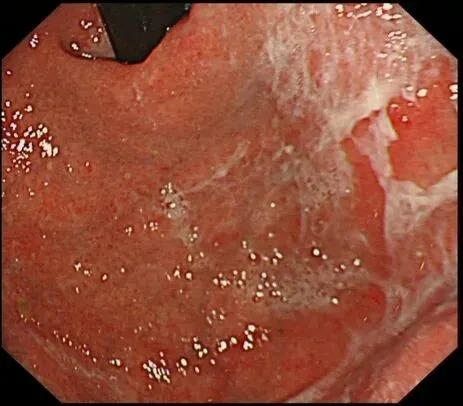

顽固性黏液(sticky adherent dense mucus):多呈灰黄色、黄白-乳白色,黏稠度高,附着于胃壁不易剥离,强行去除容易出血,也常有人称之为酒糟样固形物,多见于自身免疫性胃炎(AIG)进展期患者。

顽固性黏液case1,确诊为A型胃炎患者👇

文献报道此类型黏液因水洗不易去除,为产尿素酶弱阳性细菌的立足之处,为“泥沼除菌”的原因。

夹带小小科普:泥沼除菌(endless eradication) 通常指在自身免疫性胃炎(AIG)患者中,由于胃酸分泌显著降低,无论有无合并幽门螺杆菌感染,除菌治疗后胃酸仍无法恢复正常,幽门螺杆菌以外的产尿素酶杂菌(来源于口腔或肠道)仍可以在胃内栖息,检查13碳呼气试验持续阳性(文献报道非Hp感染的AIG患者13C-UBT平均值为5.4),导致反复除菌治疗后仍然“失败”。so,临床上遇到反复除菌失败的患者,需考虑到AIG的可能性